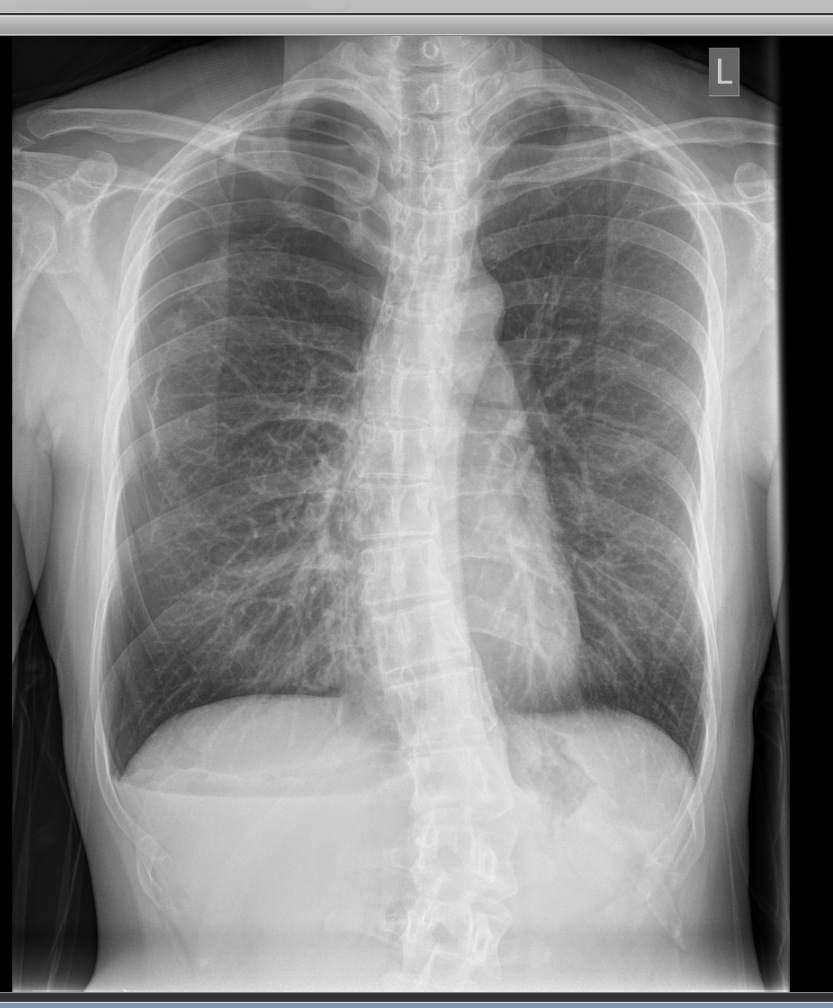

Case Presentation: A 37-year-old Korean female presented with 3-day history of worsening right posterior shoulder and chest pain, and exertional dyspnea. Review of System was otherwise negative. Past Medical History included chronic hepatitis B and an episode of pneumothorax 1 month prior. Her LMP was 2 weeks prior to presentation. On exam, she was tachypneic with absent breath sounds in the upper right lung zones. Vitals were otherwise within normal limit. Chest X-ray revealed moderate to large right pneumothorax (Fig 1). Labs were unremarkable including a normal α-1 antitrypsin assay. A chest tube was placed. On day 2 of admission the patient had video-assisted thoracoscopic surgery (VATS) with mechanical pleurodesis. Multiple diaphragmatic defects with endometrial deposits were found. The chest tube remained in situ for the duration of the hospital stay and removed 24 hours prior to discharge (Fig 2). Pelvic ultrasound was unremarkable and she was started on oral contraceptive pills.